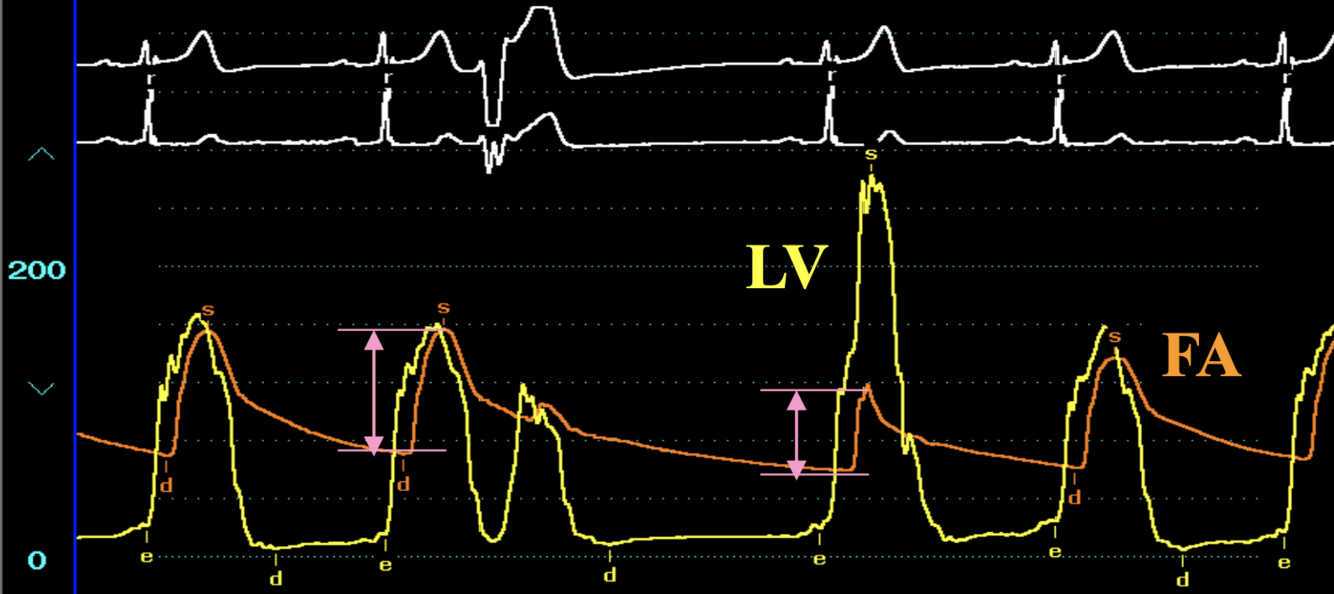

HOCM - Brockenbrough sign

How can you differentiate AS and HOCM on intracardiac pressure tracings?

Post-PVC